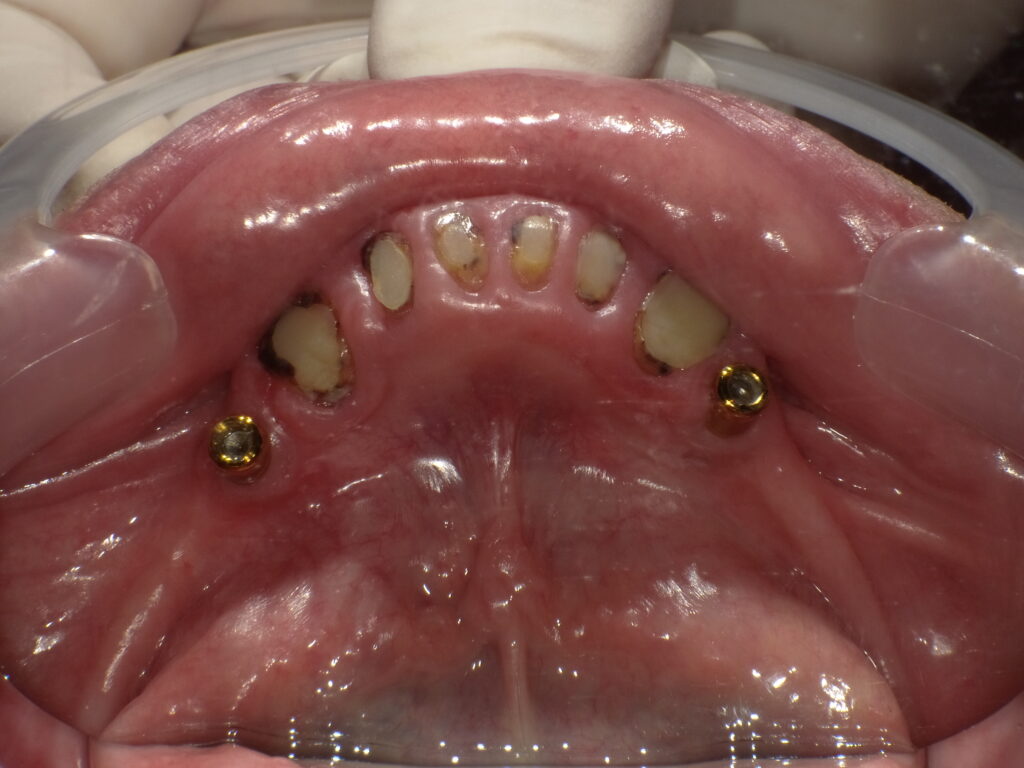

症例一覧 インプラントロケーター義歯症例1 2025.12.18 user comment…. user comment…. 治療内容インプラントロケーター義歯治療期間準備中 ホワイトニング症例4 前の記事 ワンデーTREATMENT(セレック治療)症例1 次の記事